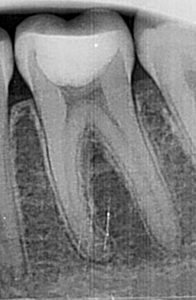

Exemplu: Un premolar doi superior – în mod obișnuit cu un singur canal – a fost tratat de două ori fără succes. Sub microscop s-au identificat trei canale, fapt care explică recidiva. Pe radiografia postoperatorie se observă obturația tridimensională completă a tuturor canalelor și prezența unor puncte albe în treimea rădăcinii, corespunzătoare canalelor colaterale tratate și obturate corect.

Premolarul doi superior, tratat anterior de două ori fără izolare, microscop sau laser, a recidivat. Datorită microscopiei, s-au descoperit trei canale, o raritate (incidență 0,5–1%). Radiografia postoperatorie arată obturația completă tridimensională, inclusiv a canalelor colaterale, realizată cu ajutorul laserului Erbium, care a asigurat curățarea integrală a sistemului endodontic.